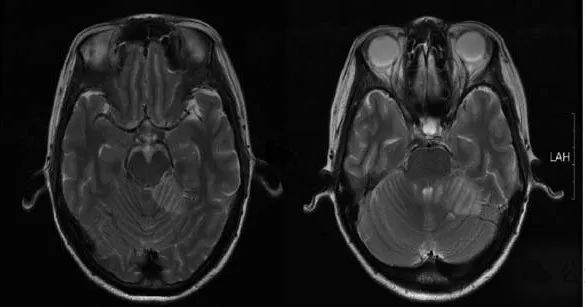

图1 一例小脑出血